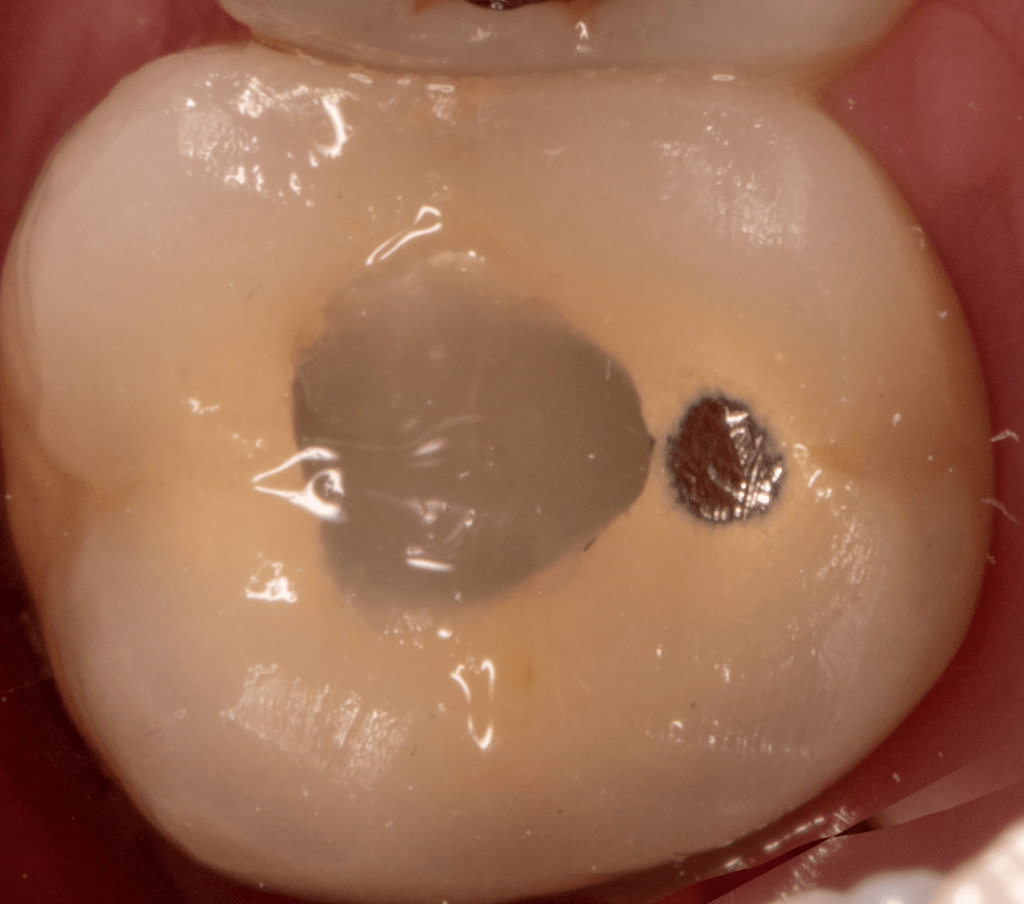

Fisura, remoción amalgama para explorar

Molar superior